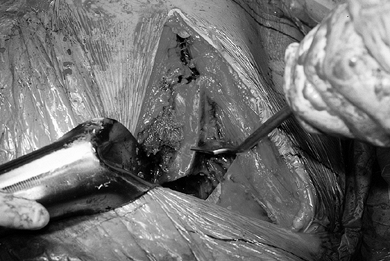

Figure 104.1.

Preoperative radiographic evaluation of the hip. This patient has avascular necrosis of the hip and is being evaluated for an intertrochanteric osteotomy. A: AP view. B: Frog-lateral view. C: AP view in adduction. D: Postoperative AP radiograph after valgus osteotomy. E: Postoperative lateral view. F: AP view after hardware removal showing good preservation of the joint space. G: Lateral view after hardware removal. |

Functional views of the hip with the femur in abduction and adduction

intertrochanteric osteotomy (ITO) (Fig. 104.1A, Fig. 104.1C).

approximates the position of the joint after a valgus–extension ITO (Fig. 104.1C).